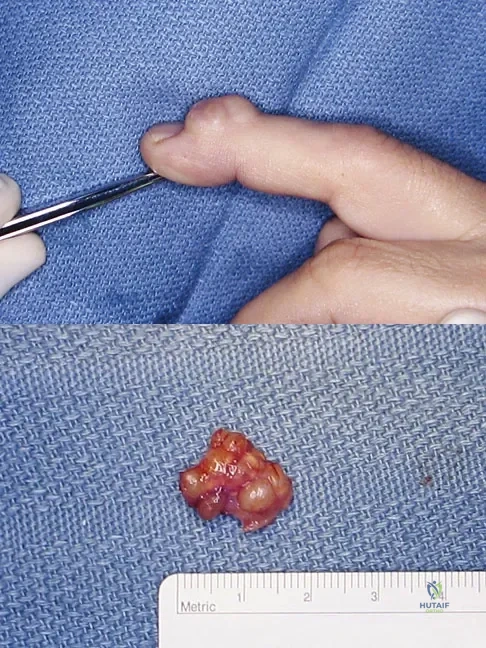

A 58-year-old woman has had a slowly progressing mass over the distal interphalangeal (DIP) joint of her dominant hand with a worsening deformity of her nail. She has no significant medical history but underwent bilateral knee arthroplasties 1 year ago. Radiographs reveal a small osteophyte at the DIP joint dorsally. A clinical photograph and a biopsy specimen are shown in Figures 76a and 76b. What is the most likely diagnosis?

Explanation